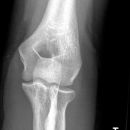

Fat Pad Sign

nicht dislozierte Radiusköpfchenfraktur